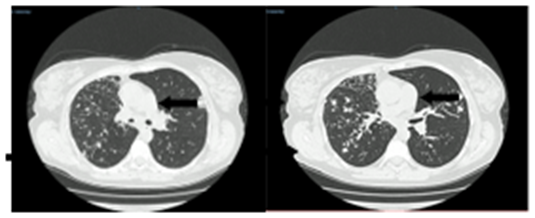

При МСКТ ОГК от 08.04.2024 по сравнению с данными от 24.03.2024 динамика в сторону незначительного уменьшения размеров, рассасывания перифокальной инфильтрации некоторых очаговых теней и фокусов в обоих легких. КТ-картина более характерна для диссеминированного процесса в легких (рис. 2).

Рис. 2. МСКТ ОГК от 08.04.2024: Во всех отделах легких с обеих сторон очаги и фокусы до 2,1 см, средней и малой интенсивности, с нечеткими контурами, сливного характера. Источник: составлено авторами по результатам данного исследования